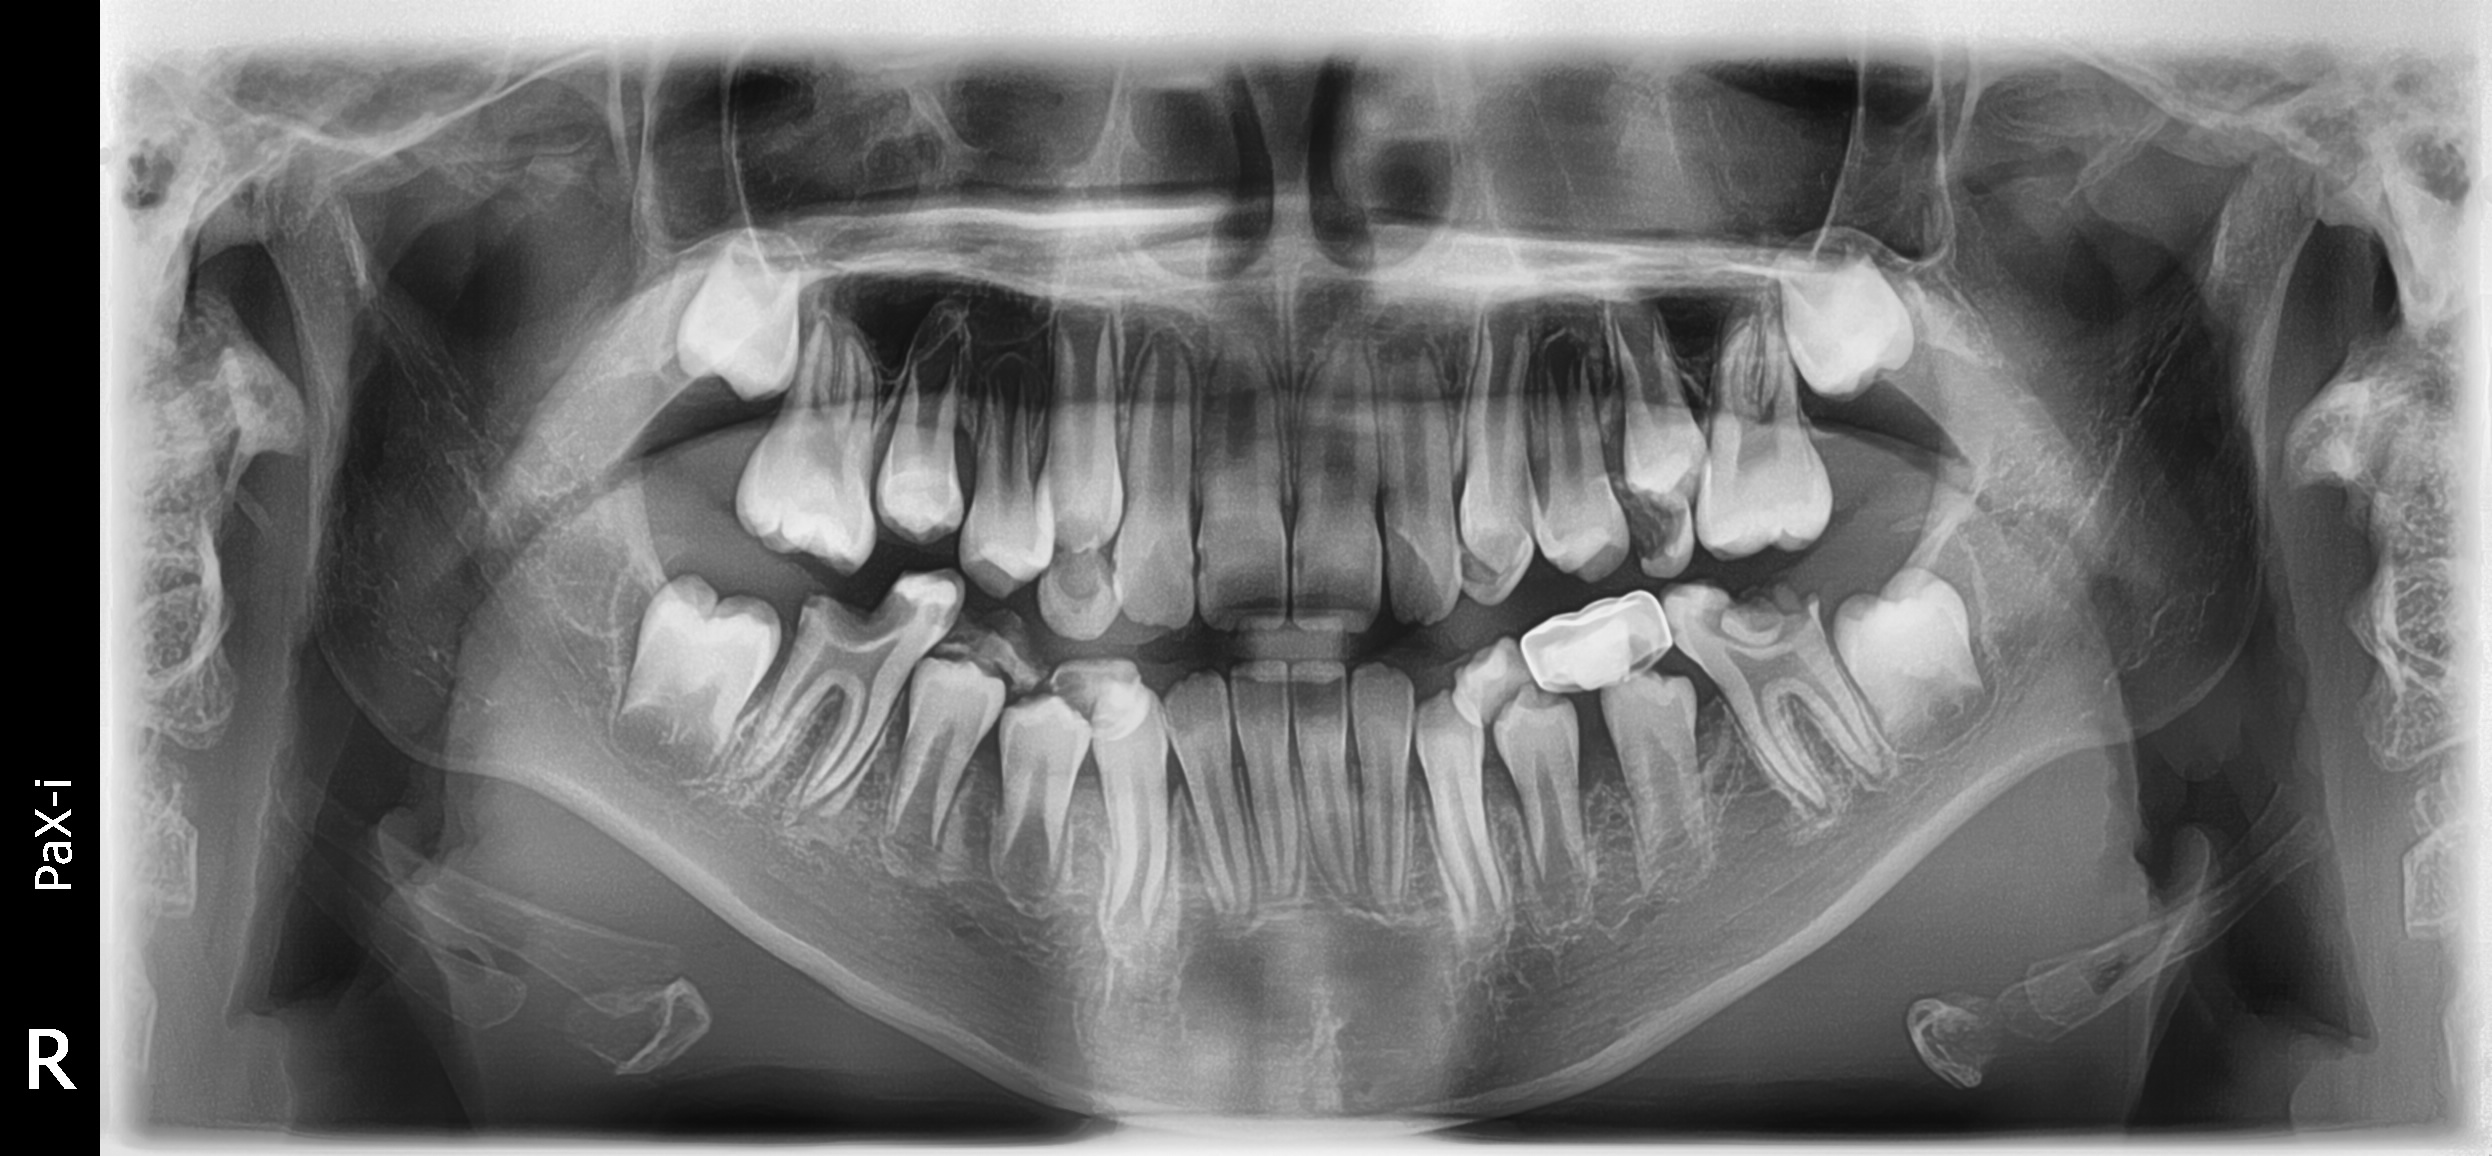

환아의 치료 전, 엑스레이와 구강 내 사진입니다. 거의 모든 치아에 충치가 있습니다. 특히 아래 어금니는 치아의 절반 넘게 충치로 깨져 없어진 상태입니다. 무서워서 빼야 할 시기를 한참 넘긴 남아있는 유치들도 많습니다. 그리고 영구치 윗니 앞니에 사이 충치가 보이네요.